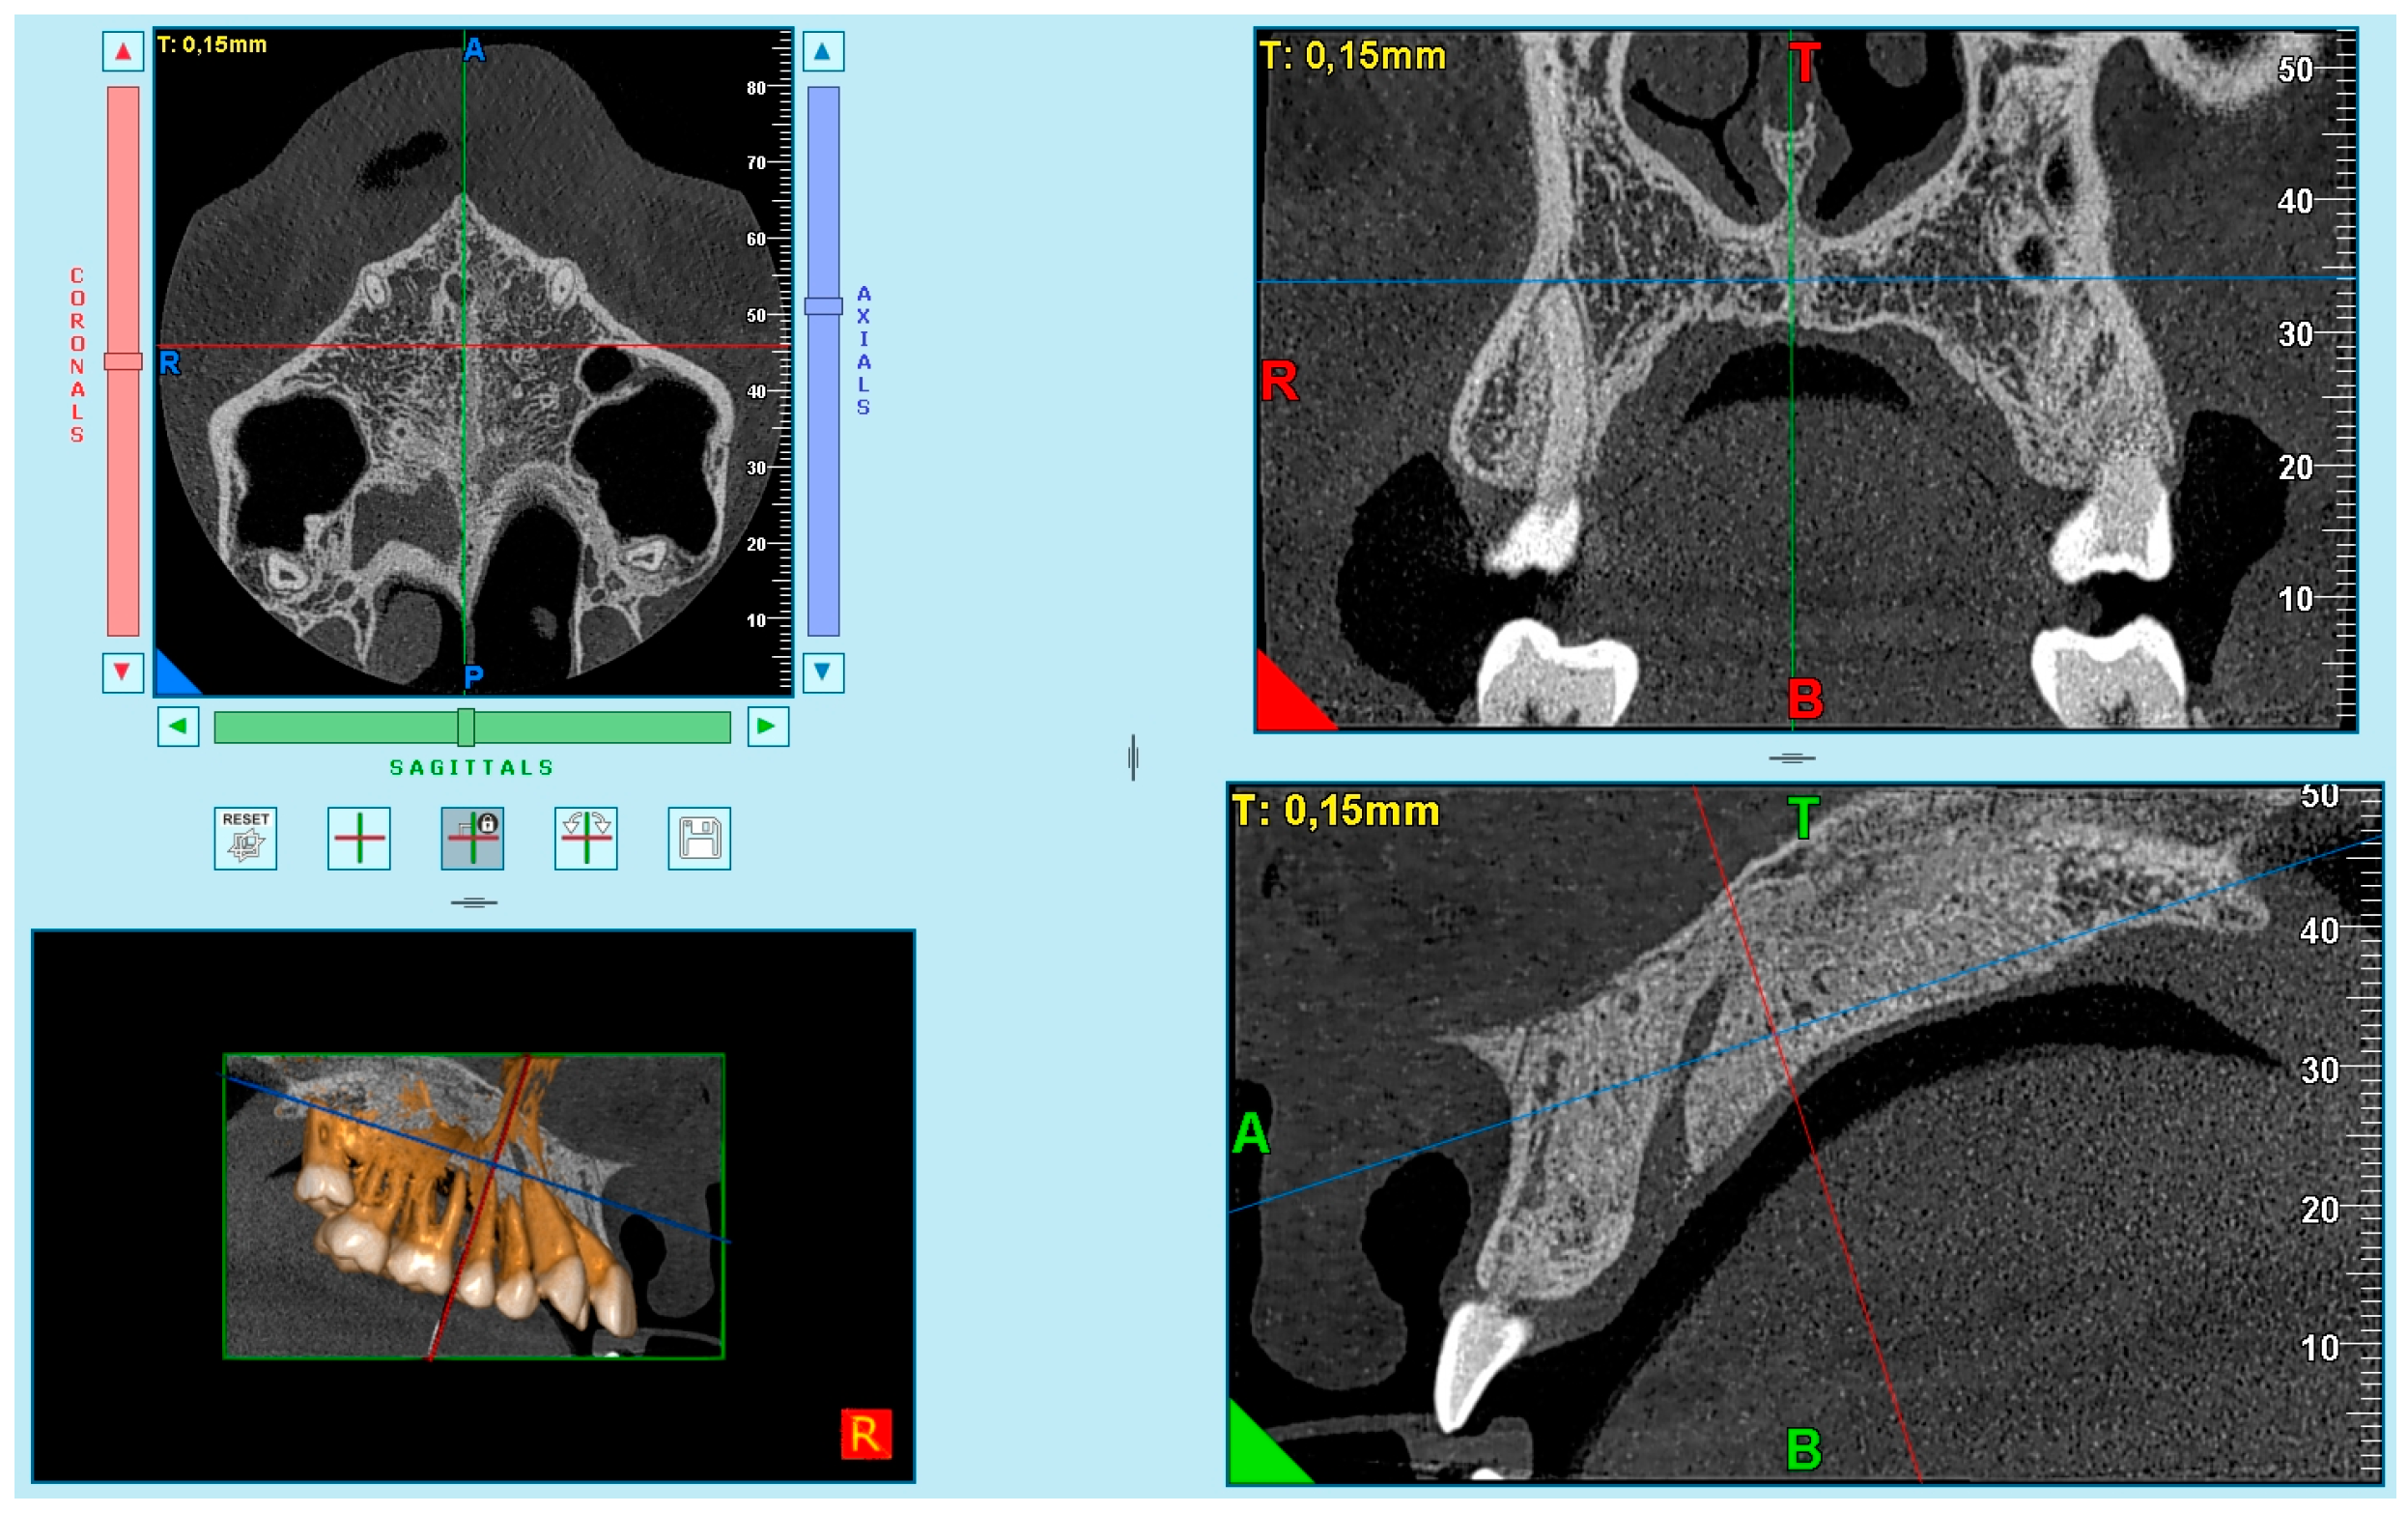

One experienced radiologist (I.G.C.) assessed all images and selected the best axial image according to the method of Angelieri et al. [40] (Figure 3). Subsequently, these images were saved as JPEG files and arranged sequentially in a presentation by the principal investigator (P.S.V.) (PowerPoint for Mac 2008; Microsoft, Redmond, Wash). The images were identified only by numbers. No change in contrast or brightness of these images was undertaken. Each patient was classified by the radiologist (I.G.C.), who was blinded, using a computer with a high-definition display in a dark room. This evaluation was considered the ground truth (the term “ground truth” is more frequently used regarding a consensus of radiographic interpretations or reliable interpretations). Consensus among radiographic interpretations or more reliable interpretations should not be considered a gold standard, because a gold standard would require histologic or microcomputed tomography examination of specimens.

Figure 3. Method of Angelieri et al. [40] in CBCT. (A) The midpalatal suture is seen as a relatively straight radiopaque line. (B) The midpalatal suture appears as a scalloped line of high density. (C) Two radiopaque, scalloped and parallel lines are separated by areas of low radiographic density. (D) The palatine bones become more radiopaque, and the suture is not visualized in this sector; it is only visualized as two scalloped high-density lines at the midline on the palate bone. (E) It is no longer possible to see the suture along the maxillary and palatine bones, which indicates that fusion has occurred in the maxilla.